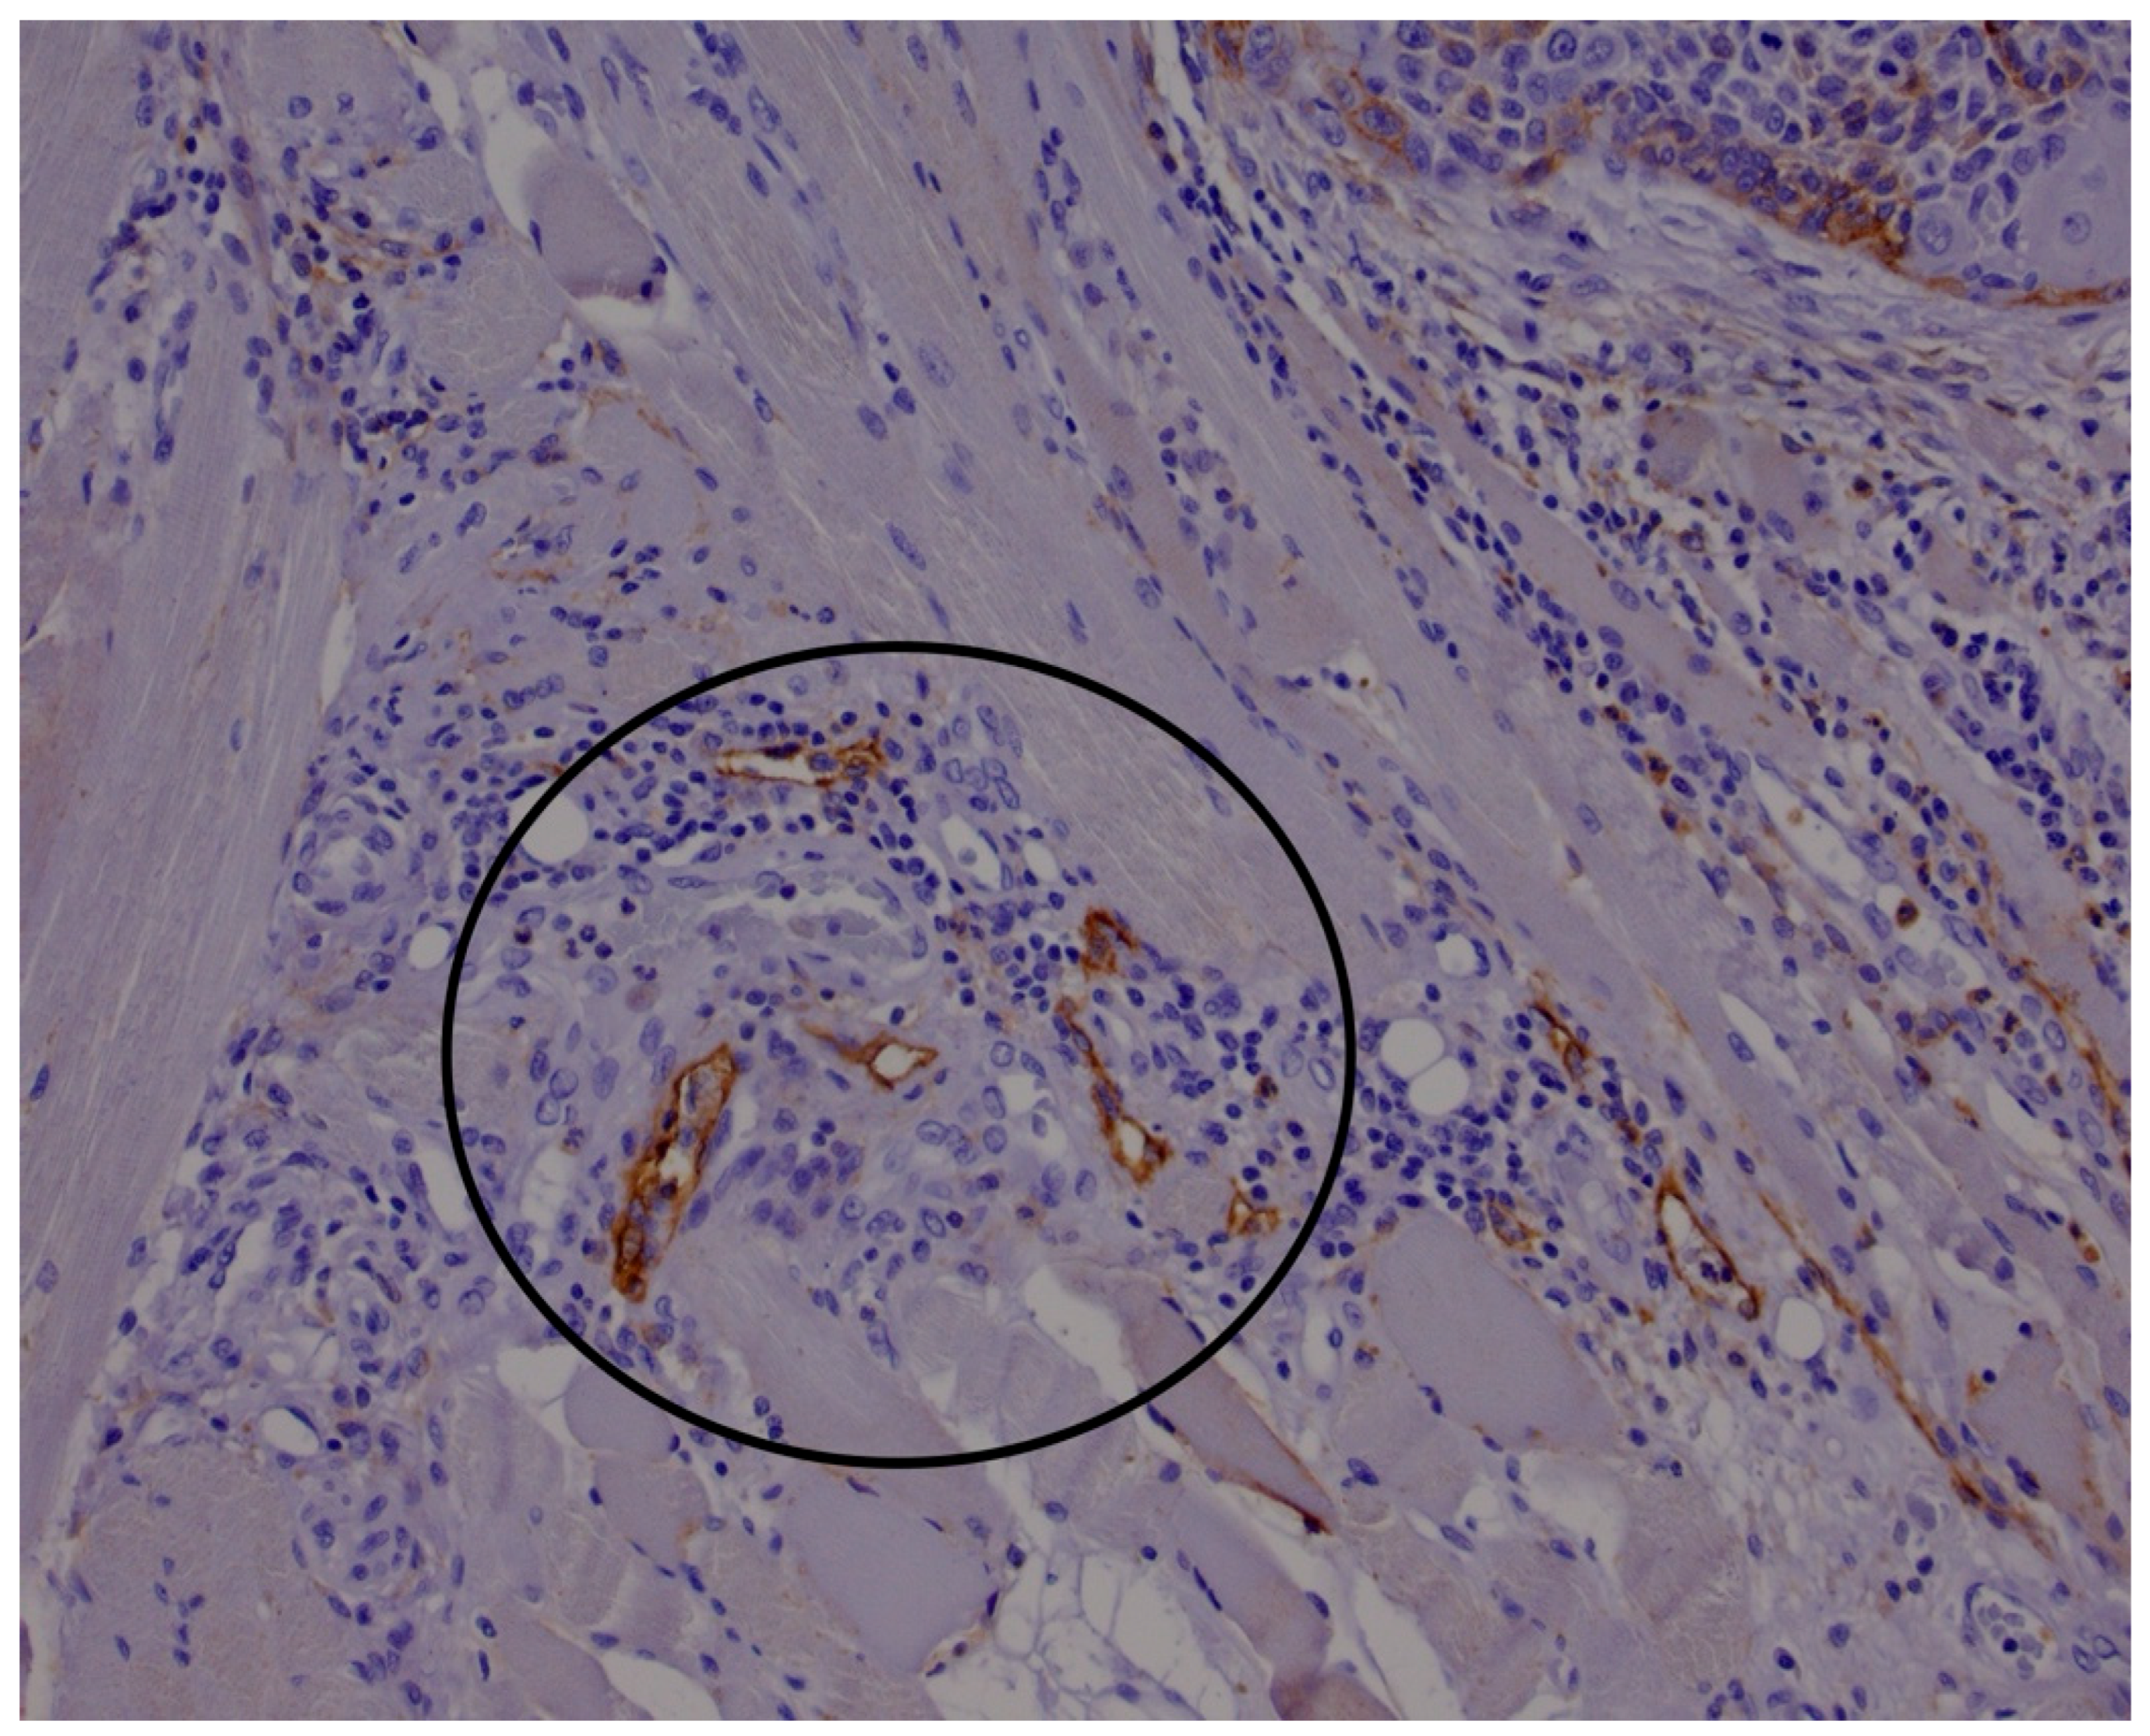

2.1. Histological and Immunohistological Analysis

- Marinho, V.F.Z.; Sanches, F.S.F.; Rocha, G.F.S.; Metze, K.; Gobbi, H. D2-40, a Novel Lymphatic Endothelial Marker: Identification of Lymphovascular Invasion and Relationship with Axillary Metastases in Breast Cancer. J. Bras. Patol. E Med. Lab. 2008, 44, 45–50. [Google Scholar] [CrossRef]

- Agarwal, D.; Pardhe, N.; Bajpai, M.; Gupta, S.; Mathur, N.; Vanaki, S.S.; Puranik, R.S.; Mittal, M. Characterization, Localization and Patterning of Lymphatics and Blood Vessels in Oral Squamous Cell Carcinoma: A Comparative Study Using D2-40 and CD-34 IHC Marker. J. Clin. Diagn. Res. JCDR 2014, 8, ZC86–ZC89. [Google Scholar] [CrossRef]